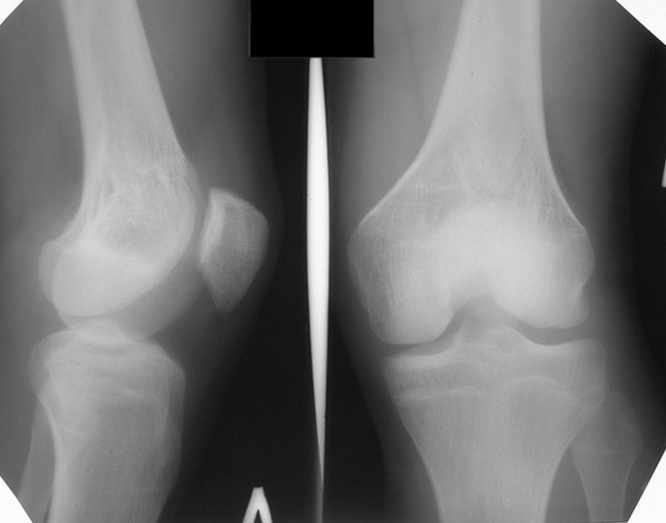

Больной Н., мужчина 18 лет с укорочением бедра и рекурвацией коленного сустава.

Из анамнеза: огнестрельное сквозное пулевое ранение бедра 9 лет назад в н/3 левого бедра. Раны зажили без гнойных осложнений. Жалобы на укорочение левой нижней конечности и нестабильность в коленном суставе. При обследовании выявляется рекурвация коленного сустава. Абсолютное укорочение порядка 5см, стоя 8 см (за счет рекурвации). Имеется умеренный компенсаторный сколиоз. С передне-наружной стороны располагается рубец от входного отверстия, с задне-медиальной стороны от выходного. Можно предположить повреждение при травме зоны роста бедренной кости и задне-внутренних стабилизирующих структур коленного сустава.

A male 18 years old with shortened femur.

Trauma 9 ears ago: gunshot wound with bullet of the left knee. It Is Reeked have healed without festering complications. The patient have shorter femur and recurvatum instability of knee joint. Absolute shortening is 5 cm, at standing up 8 cm (genu recurvatum). The input scar is situated on the antero-lateral side and output scar is on the postero-medial side. It is possible to expect damage by trauma of the growing zone of the femur and back-internal stabilizing structures of the knee joint. We discuss the treatment options: to begin with lengthening of the femur or preferably with stabilizations of the knee joint. What is the optimal level to produce the lengthening of the femur in this case.